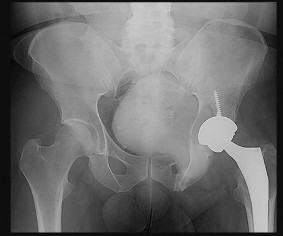

Figures 7a through 7d are the radiograph, MR images, and biopsy specimen of a 35-year-old man who has a painful, slowly enlarging knee mass. Which chromosomal translocation is characteristic of this pathology?

Synovial sarcoma is a soft-tissue sarcoma that usually occurs in young adults. Synovial sarcoma often causes pain, unlike most soft-tissue sarcomas, which generally do not cause pain. Imaging characteristics include soft-tissue calcifications on plain radiographs and a heterogeneous mass that is generally isointense to muscle on T1-weighted images and hyperintense to muscle on T2-weighted images. There are biphasic and monophasic types of synovial sarcoma. The biphasic

type, which is depicted here, has both spindle cell and epithelial components and will stain for both vimentin and cytokeratin. More than 90% of patients with synovial sarcoma have a characteristic genetic translocation of t(X;18), which results in the fusion protein SS18-SSX. This translocation can be stained for use of florescence in situ hybridization technology. t(11;12) is seen in Ewing sarcoma. T(9;22) is seen in extraskeletal myxoid chondrosarcoma. t(12;16) is seen in myxoid liposarcoma.